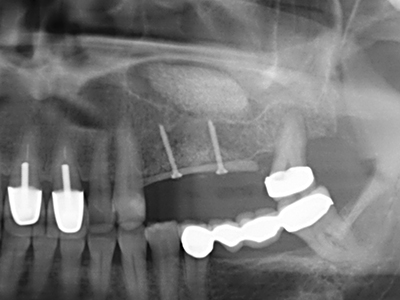

Indication: Preparations close to nerve tissue

Indication: Apical resection

When surgical procedures are performed on bone in the immediate vicinity of sensitive structures such as blood vessels or nerves, rotary instruments pose a significant risk of iatrogenic injury. Piezoelectric devices can be helpful for preparation of bone covers and removal of hard tissue close to nerves, particularly for exposure of nerves after iatrogenic injury but also during nerve lateralization for resective and reconstructive procedures or implant placement (Fig. 17-20). Light contact between the piezotip and the nerve does not generally result in damage but proceeding incautiously with saw-like motions or attachments where a residual bone substrate remains may cause temporary or even permanent nerve damage. However, the risk of damage is considered to be substantially lower than when using saws or milling instruments (Pereira, Gealh et al. 2014).